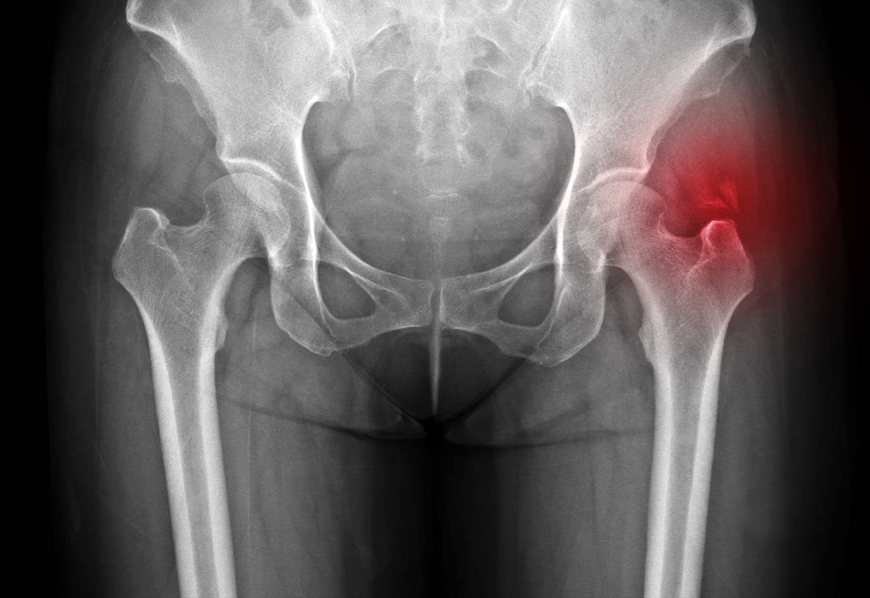

고관절은 골반뼈와 윗다리뼈 사이에서 이루는 관절을 뜻하며, 엉치부위보다는 주로 사타구니 주변의 통증을 유발합니다. 대개의 사람들이 엉치부위의 통증을 호소할 경우에 고관절 보다는 주로 허리 문제에서 방사통 형태로 내려오는 문제일 가능성이 제일 높으며, 그 외에는 엉치 부위의 둔근(엉덩이근)의 근육 문제로 기인할 가능성이 있습니다. 그러므로 엉치부위 주변의 통증이 있을 경우 골반과 함께 허리에 대한 평가도 같이 이루어져야 합니다.

석회성힘줄염

어깨 이외에 고관절 주변에도 석회성 힘줄염이 호발할 수 있으며, 역시 갑자기 발생하는 허벅지 옆쪽 주변의 극심한 통증을 호소하며, 석회가 있다고 해서 반드시 제거할 필요는 없으며, 대개 흡수기에 동반되는 염증반응으로 증상이 발생하므로 염증 완화 목적의 약물치료, 물리치료에 충분한 증상완화가 없다면, 주사치료 병행이 도움됩니다. 또한, 체외충격파 치료의 경우 석회가 주변으로 흡수되도록 하여 석회를 줄이는데 도움되므로 재발성 석회성 힘줄염 등에 시행하게 됩니다.